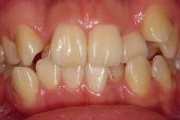

(その2)↑.

このケースは,下顎が横(右側)に大きくズレていて,上顎の歯並びに凸凹もみられます.

↑スプリント療法と,マルチブラケット矯正を併用して治療を行いました.下顎にオクルーザルスプリントを使用しながら,上顎の歯列アーチの拡大および個々の歯の整列を行った結果,下顎の右方偏位は改善し,上下の歯列の正中はほぼ一致するようになりました.